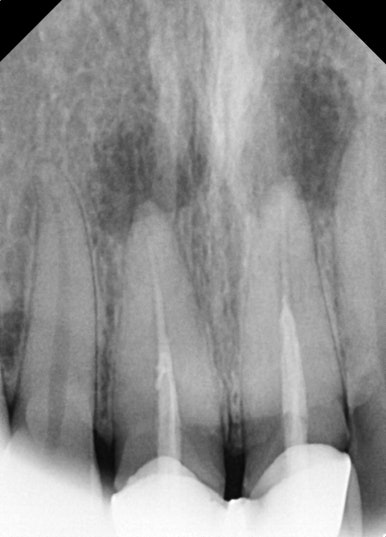

📸 케이스 5: #11, #21 앞니 Re-Endo

- 큰 염증과 통증

- 단순 재신경치료만으로는 한계가 있어

→ 치근단 수술 또는 발치+임플란트 가능성도 설명

- 반복 소독 후 염증 개선 → MTA + GP Cone 충전

✅ 크라운 재보철까지 완료